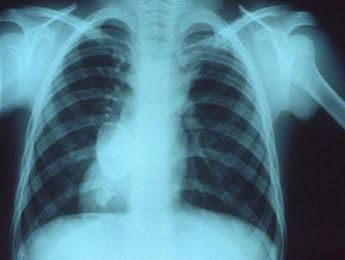

Symptoms of atelectasis

What are the signs and symptoms of atelectasis? Trouble breathing (shortness of breath) Increased heart rate. Coughing. Chest pain. Skin and lips turning blue.